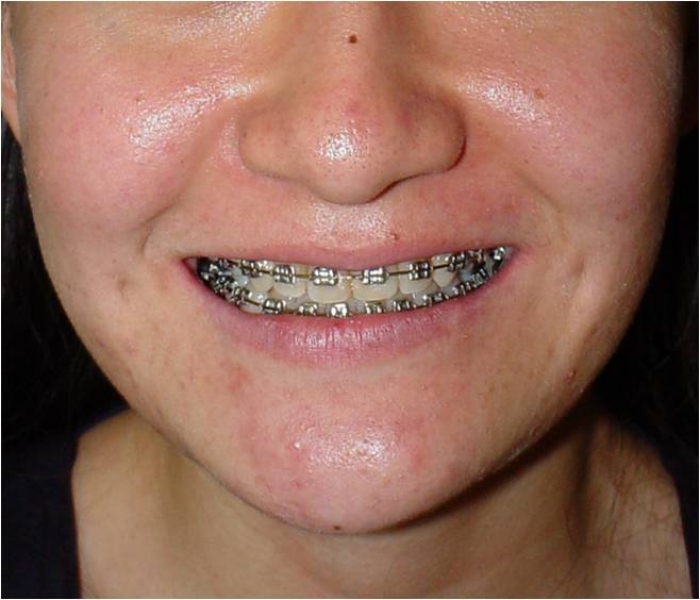

Imagem inicial com assimetria de face